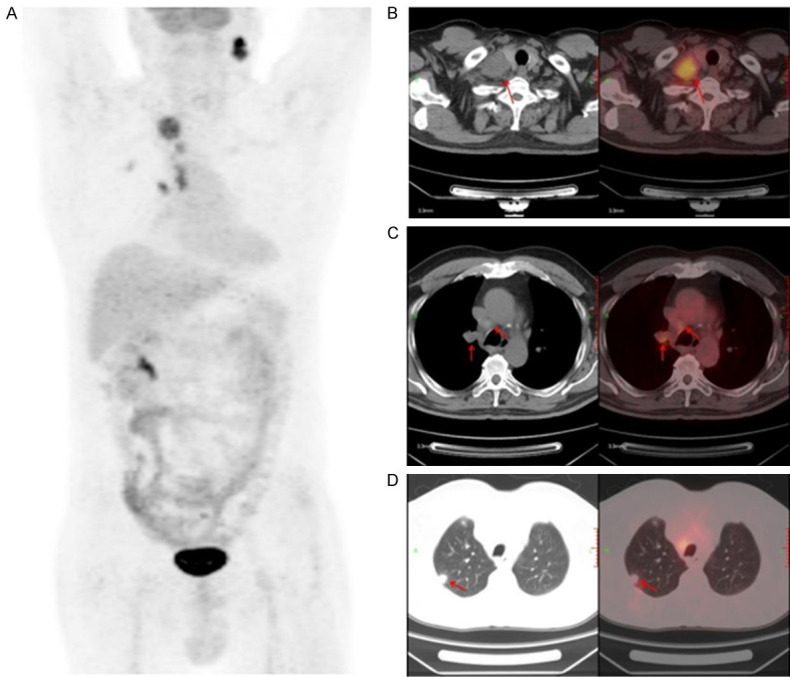

The patient was diagnosed with stage IIIC (cT3N3M0, according to 8th AJCC staging system) lung adenocarcinoma via needle biopsy of cervical lymph node and positron emission computerized tomography and computer tomography (PET-CT) (Figure 1). Next-generation sequencing (NGS) testing showed that this patient harbored STK11 mutation (p.D176Y, c.526G>T, 11.41%), TP53 mutation (p.M246V, c.736A>G, 8.81%) and ATM mutation (p.L2633, c.7898dupT, 9.23%) (Table 1).

Figure 1.

PET-CT scan of baseline lesions. Positron emission computerized tomography and computer tomography (PET-CT).